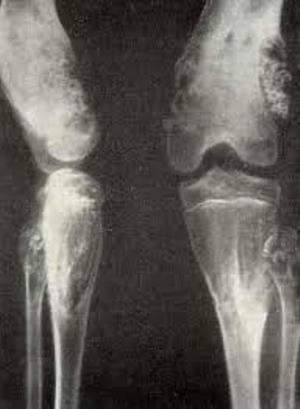

Патологическое состояние характеризуется отставанием в росте и деформированием поврежденных участков. Зачастую отмечаются патологические травмы — перелом. На рентгеноснимках длинных трубчатых костей можно определить колбовидные расширения метафизов при нормальной формы диафизах. Костный рисунок в метафизной части видоизменяется в сторону неравномерного исчерченного просветления с истончением кортикального слоя. На рентгенографическом снимке кистей и ступней визуализируются уменьшение длины и деформирование фаланг. Местом локализации просветлений выступают центральные отделы, но корковый слой обычно не изменяется, при крупных энхондромах выявляется выпячивание корковой пластинки.

Патологический процесс характеризуется уменьшением длины трубчатых костей, они уплощаются с наличием деформирования и искривления, фиксируются патологические переломы, в некоторых случаях экзостозы. Рентгенологические проявления – укорачиваются длинные и короткие кости, визуализируются многочисленные односторонние энхондромы.